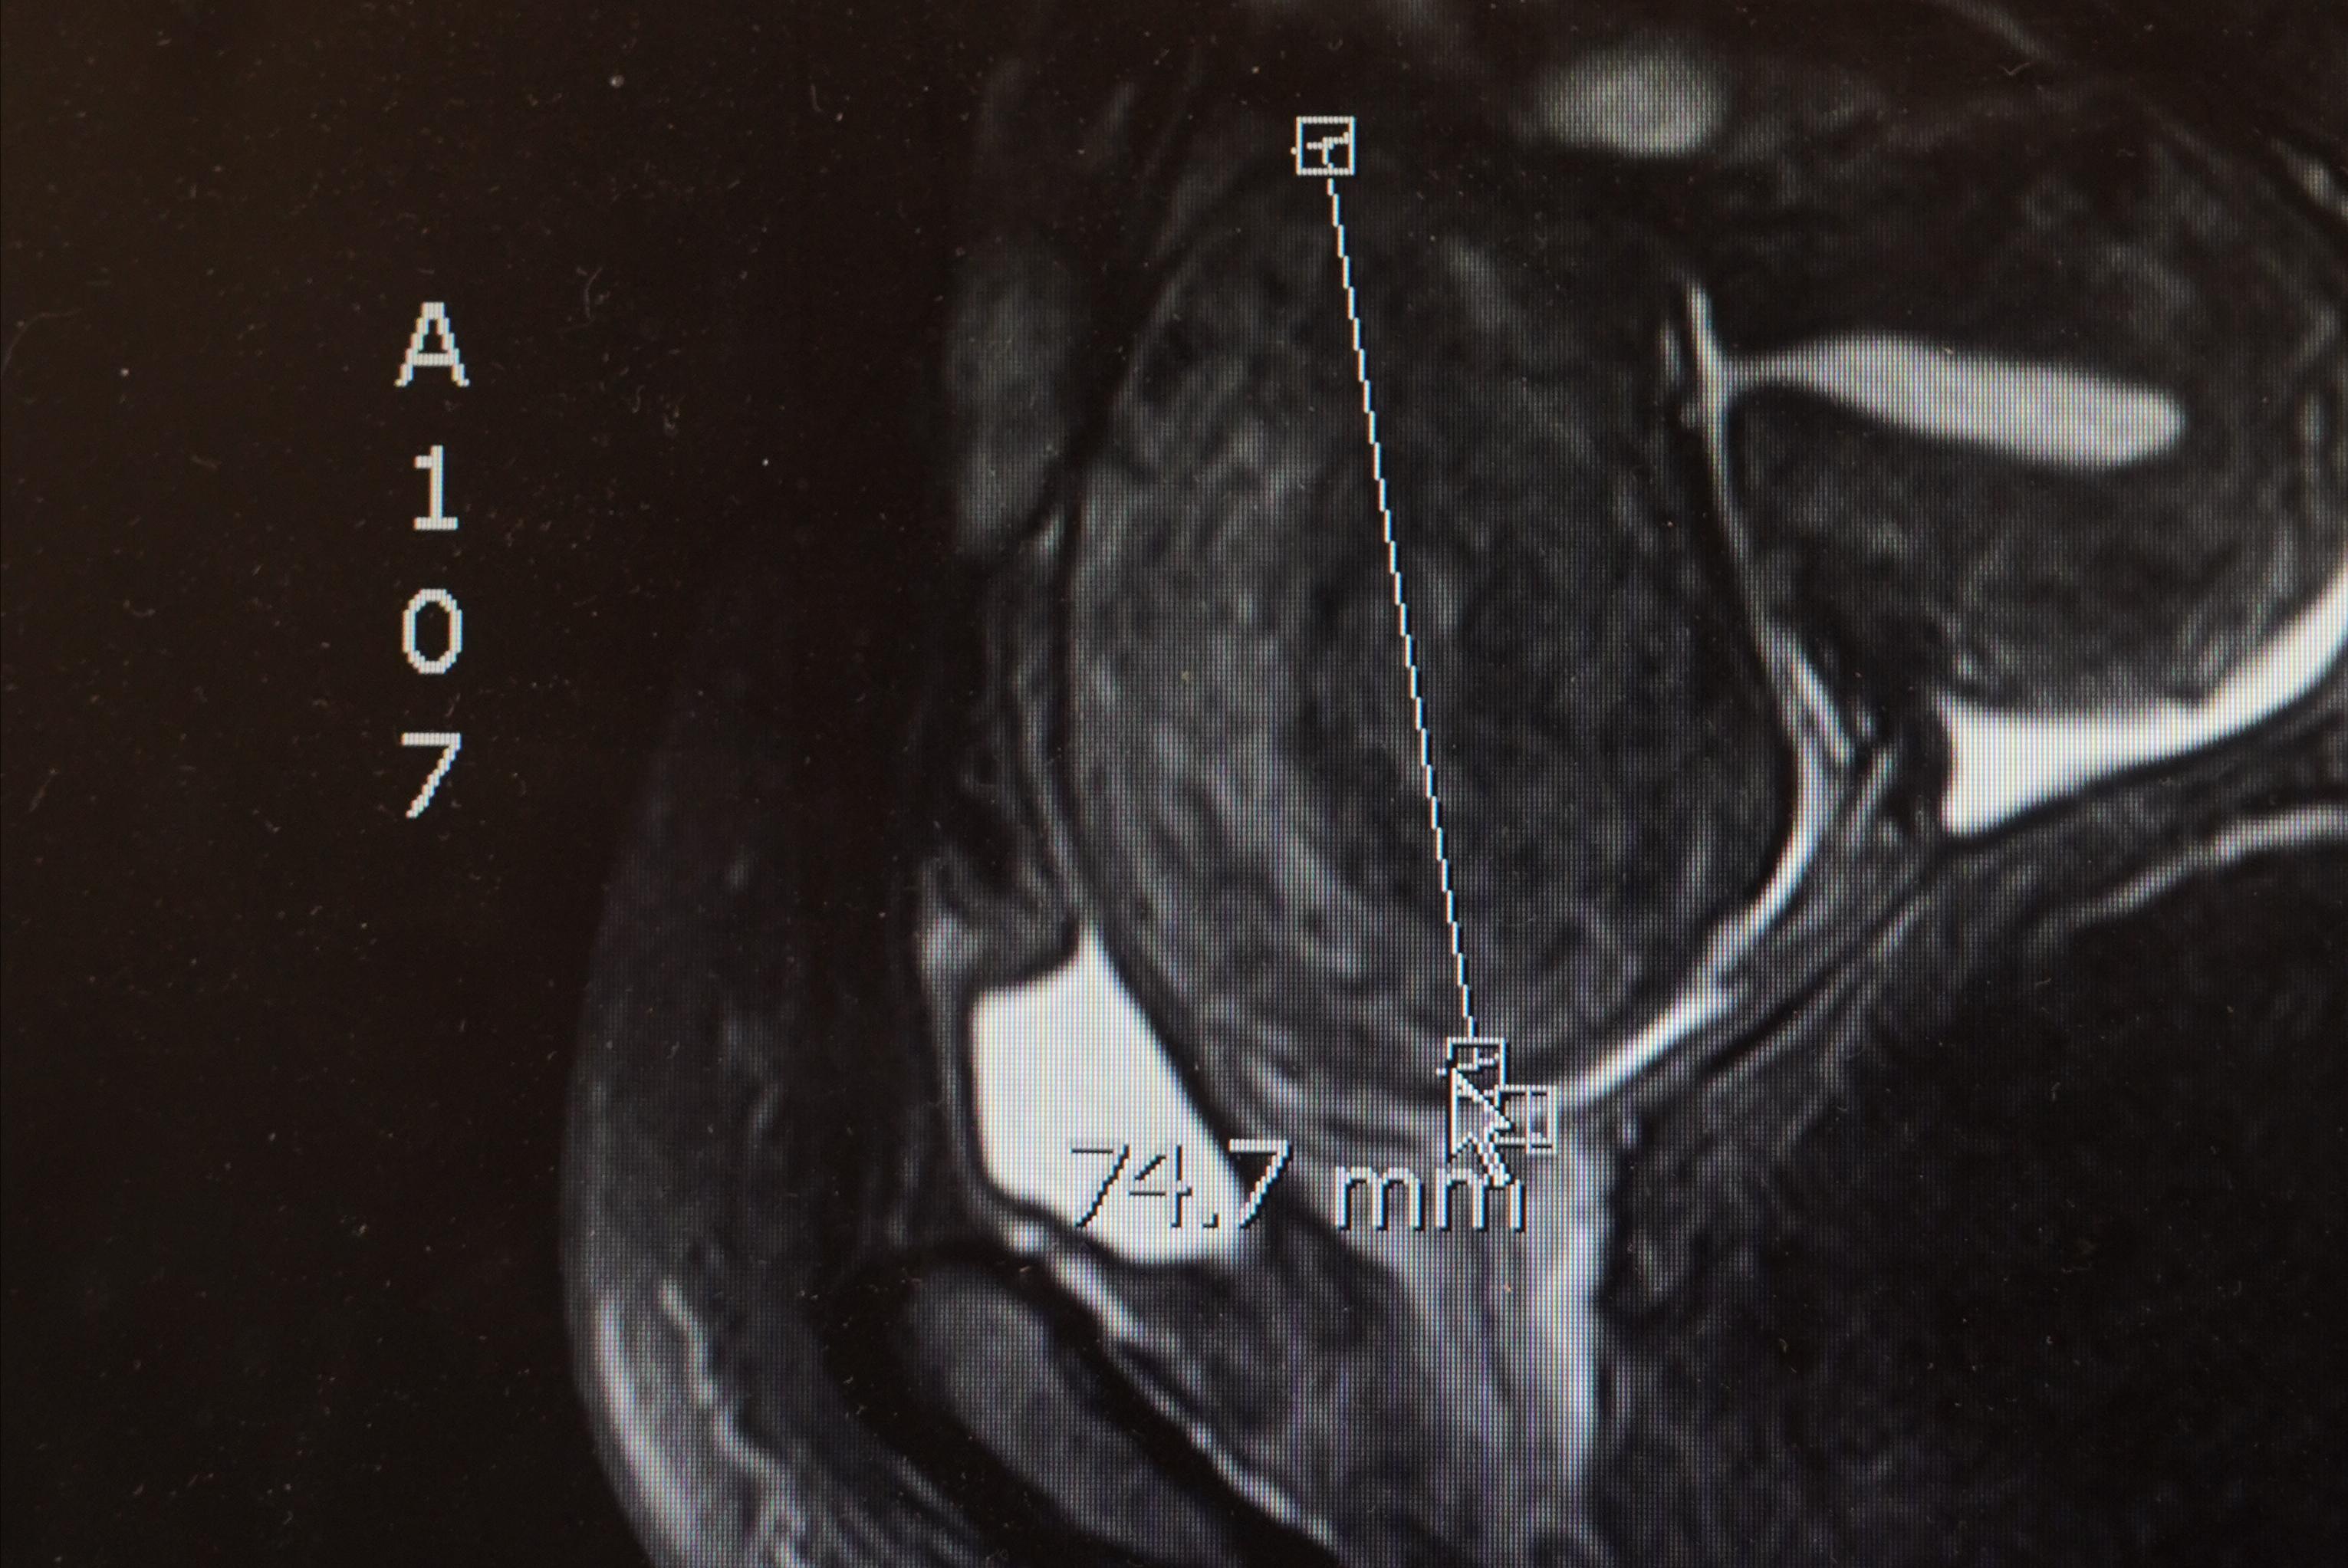

从她的CT结果看,整个子宫里,到处都是肌瘤,子宫前壁、宫底、后壁,前前后后加起来得有10多枚,大大小小散布在子宫肌壁间,浆膜下,另外,我们还在她的宫颈口看到了分叶状的息肉。

一个长得像生姜一样的子宫出现了,整个子宫增大,像怀孕4月一样,表面多个肌瘤结节状凸起,哦,工作量大了。

然后,我一个个找出那些散布在子宫里的肌瘤,一遍遍切开,取出,切开,取出,经过2个多小时,终于把10枚肌壁间肌瘤、3枚浆膜下肌瘤、1个卵巢囊肿通通切了下来。

可能是医患之间充分的沟通,加上术前评估充分,肌瘤定位准确,这台手术非常顺利, 完美的结束,手术时长2h,出血量仅有50ml,非常成功。